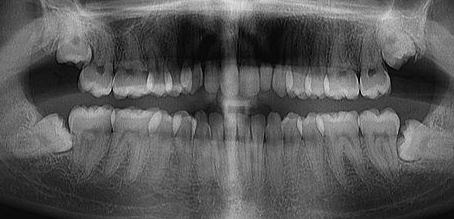

X-ray 사진을 찍고, 설명을 듣는데 제 잇몸 상태가 나이에 비해 많이 안 좋고 꽤나 내려앉아 있는 상태라고 하더라구요...ㅠㅠ

저의 처참한 잇몸 x-ray를 보고 집으로 돌아오는 길이 어찌나 어찌나 우울하던지...ㅠㅜㅠㅠ 치아랑 잇몸은 재생도 안되는데...

▲ 치아의 3분의 2를 덮고 있는 건강한 잇몸

▲(좌) 건강한 잇몸/ (우) 이미 많이 내려앉은 잇몸

▲ 이렇게 잇몸이 내려앉게 되면 미관상으로도 좋지 않은 것 같아요ㅠㅠ..